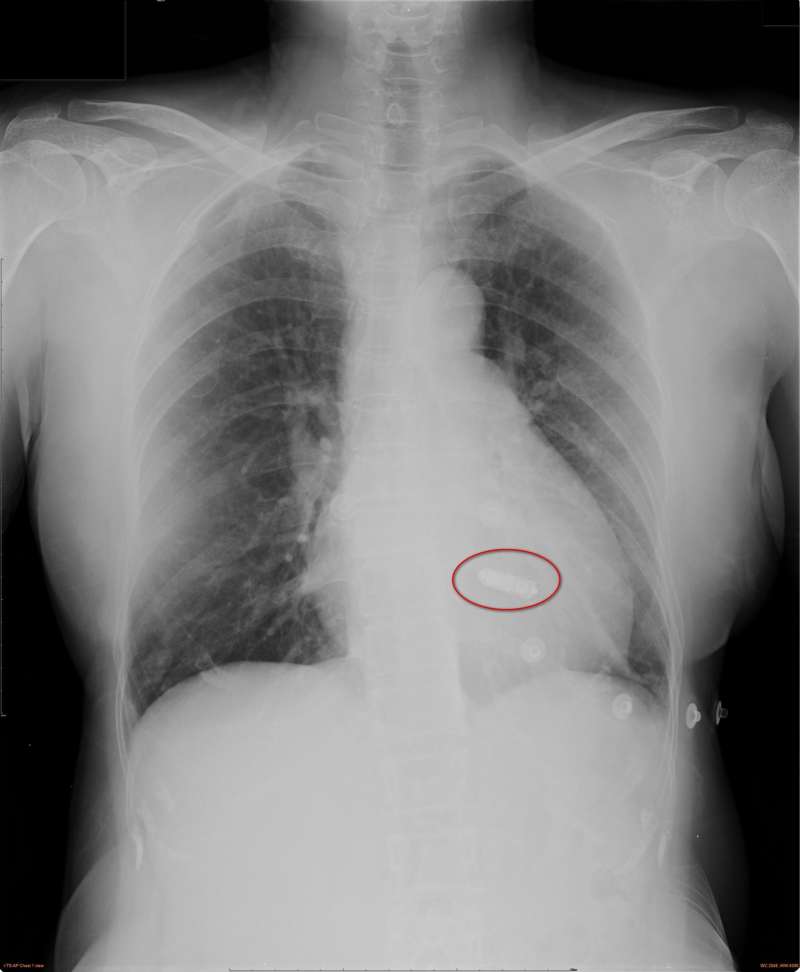

醫師林柏霖說,傳統心律調節器體積約12.7c.c.,由節律器(俗稱電池)、電極和導線組成。裝置時,採表皮局部麻醉,於胸口切開約3~8公分傷口,將電極導線穿過鎖骨下靜脈,置於心臟內適當位置,再於傷口內下方放置節律器與導線。

林柏霖強調,相較起來,無導線心臟節律系統沒有手術傷口及異物突起,手術後也不必限制動作,且一樣能達到傳統心律調節器控制心律的目的,無導線心律調節器將節律器、電極和導線整合為一外觀不到3公分高的膠囊,僅約0.8c.c.、2公克重,體積不到傳統心律調節器的1/10。

手術一樣採表皮局部麻醉,從患者鼠蹊部順著股靜脈,藉由導管將無導線心律調節器固定於右心室,移除導管後僅留下鼠蹊部約莫1公分的傷口。手術時間通常較傳統心律調節器短,平均約半小時。